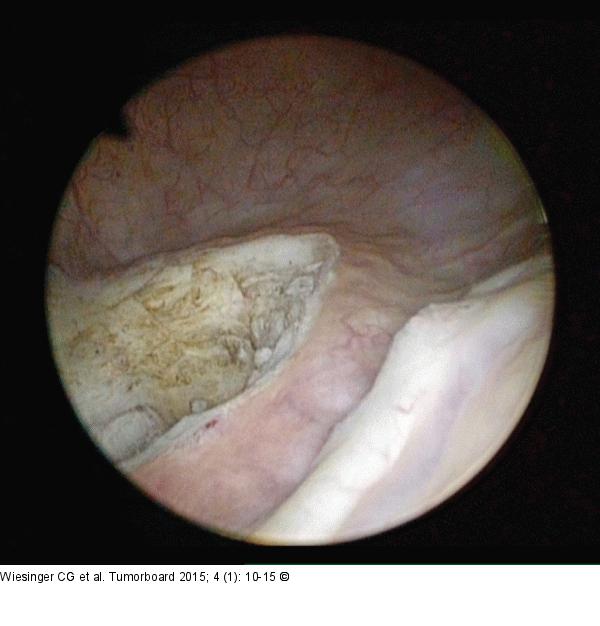

Abbildung 5: Tumorresektion Zustand nach Tumorresektion |